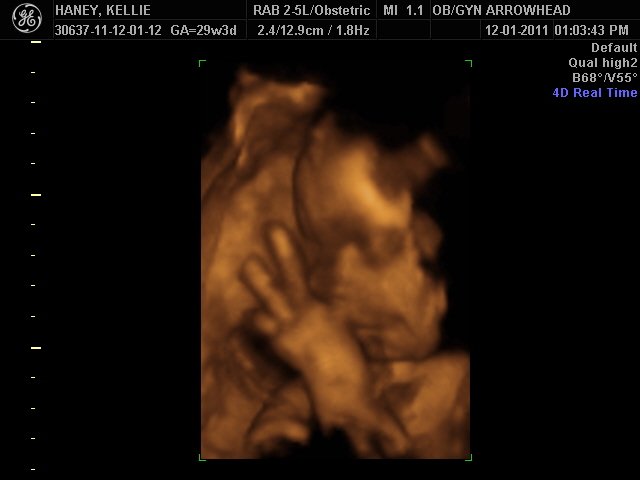

We offer complimentary 3D/4D Ultrasounds to all our OB patients around 30 weeks! The following photos are some examples of our work, shown with permission from our patients.